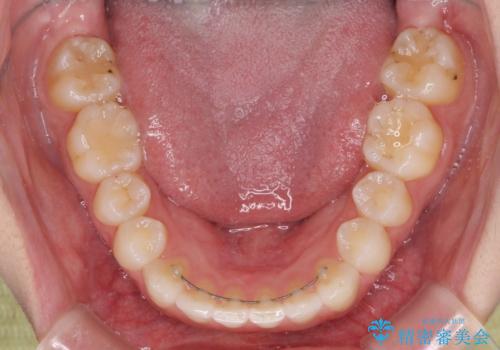

上の前歯が下の前歯を乗り越える際、奥歯がほとんど咬めない時期があり、乗り越えた後も、インビザライン特有の奥歯の咬みにくさが続きました。

咬み合わせ改善のために治療期間を要しましたが、最終的に奥歯はしっかりと咬めるようになりました。